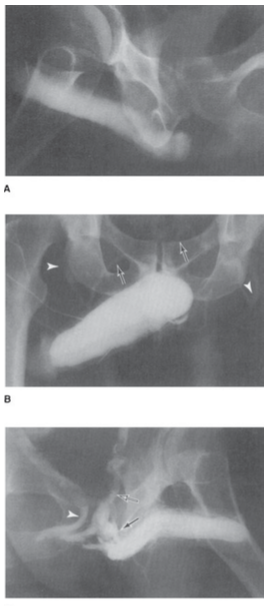

CAVERNOSOGRAFÍA

Tras la inyección de contraste y la inducción de una erección artificial se valora mediante imágenes radiológicas el sistema vascular y el flujo sanguíneo del pene.